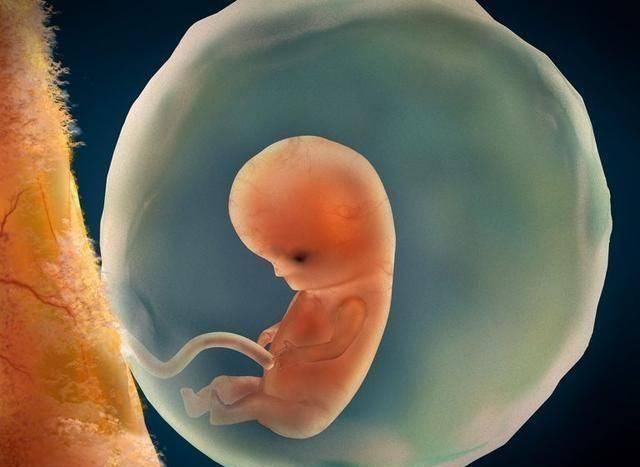

1、孕囊

孕囊是原始的胎盘组织,是怀孕最初的形态。如果孕囊在宫内,就能确定是宫内孕,属于正常怀孕。孕囊的尺寸一般在1.33厘米-1.66厘米,有椭圆形的也有圆形的。

如果是瘢痕子宫,还要确定孕囊是否是在瘢痕上,在这上面风险比较大,有子宫破裂的风险。经过评估之后,如果影响后续妊娠,会建议拿掉这个孩子。

孕囊如果不在宫内,就是宫外孕,宫外孕容易引起大出血,要及时手术处理,以免对身体健康造成威胁。